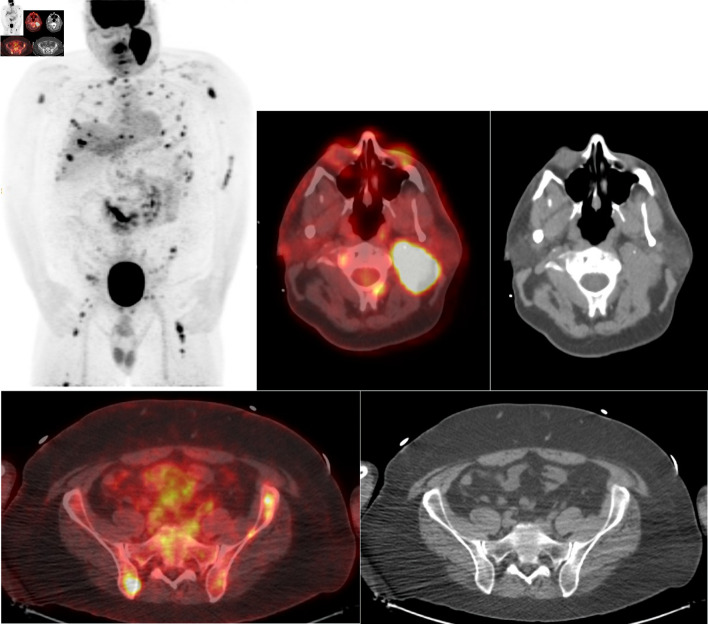

Abstract Image